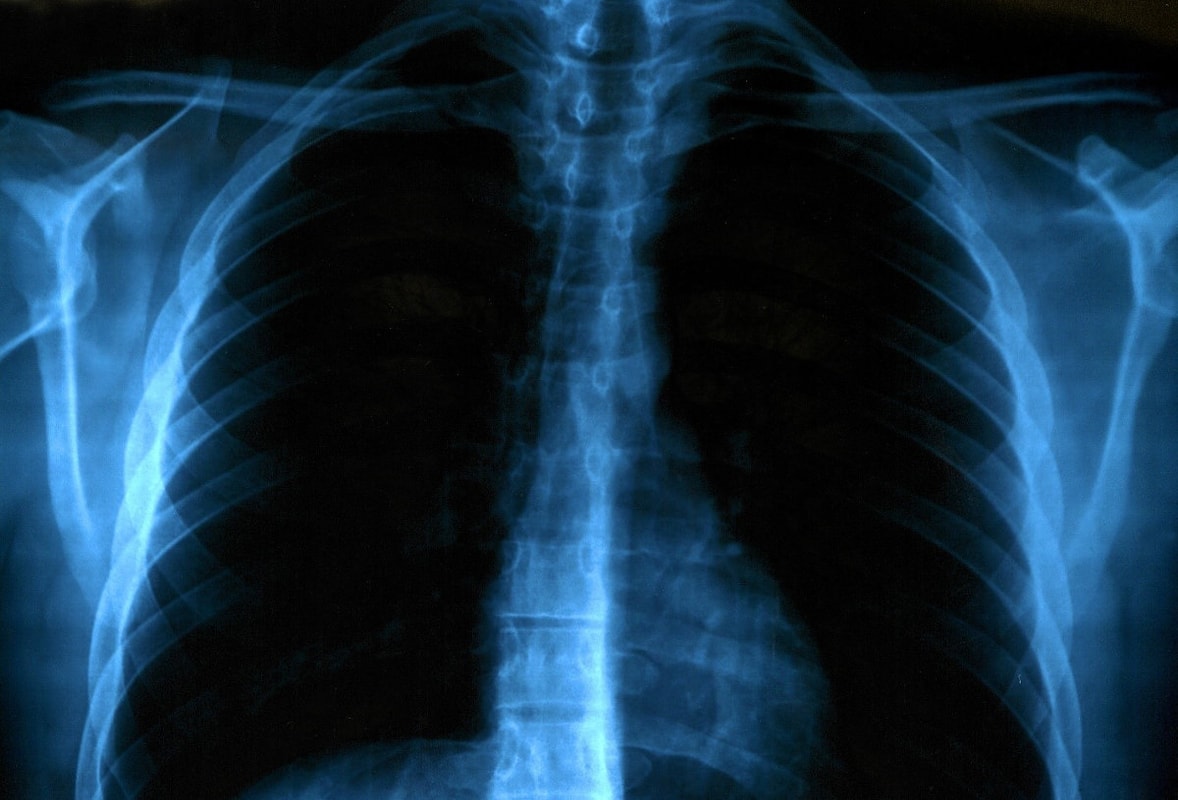

Respiratory system

Respiratory organs include the nose, larynx, windpipe and trachea. The windpipe branches into two smaller airways, and these into many smaller twigs, which end in lungs.

Through the airways, air flows from the nose, through the trachea, smaller windpipes and the smallest branches all the way to the lung bubbles (alveoli). Lungs are surrounded by a network of thin arterial and venous blood vessels (capillaries).

Breathing is performed rhythmically by a muscular-membranous plaque - the ossicles or diaphragms and ribs driven by the rib muscles. The normal rhythm of breathing at rest is about 16 times per minute.

When inhaled, oxygen-rich air travels through the airways to the lungs. The lung bubbles deliver oxygen to the red blood cells (erythrocytes), and they distribute it throughout the body and deliver it to the cells where they are "burnt" to release energy. In this process, carbon dioxide (CO2) is produced, which is returned to the veins by blood and released into the environment by exhalation in the lungs.

In casualties, we look for the existence of breathing, the rhythm of breathing, the existence of obstructions in the airways, the secretion and bleeding from the airways, the use of respiratory muscles, etc.